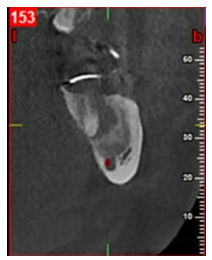

En corte transaxial se aprecia en una imagen hipodensa una cavidad quística de menos diámetro, siendo la compensación ósea mayor.

Figura 10 En una vista transaxial se observa una imagen hiperdensa compatible con crecimiento óseo en todo el hemisferio de la raíz mesial de la U.D 37. Fuente: Historia Clínica. Especialización Cirugía Bucal ULAC-IDOLA. 2022